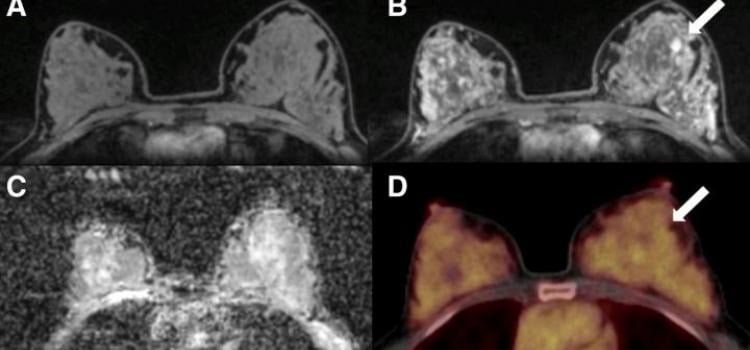

May 19, 2021 — According to an open-access article in ARRS’ American Journal of Roentgenology (AJR), increased axillary ...

December 10, 2021 — According to an article in ARRS’ American Journal of Roentgenology (AJR), MRI—with or without FDG ...